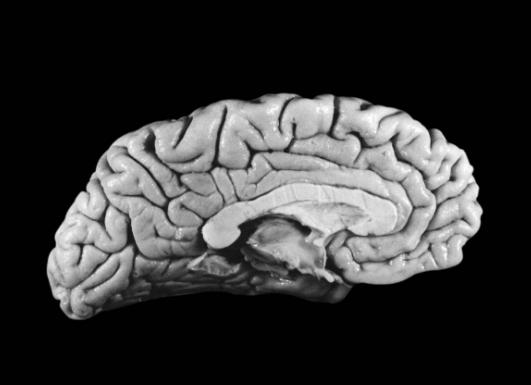

较早发表“轻脑”研究成果的是阿拉巴马大学的神经学教授保罗·安德森。经过10余年的研究他发现,爱因斯坦的大脑重量只有1230克(普通男子的大脑一般重1400克),因此他的大脑皮层比一般人薄。

安德森据此推测,爱因斯坦的大脑神经细胞密度比普通人高,使得传递信息的效率大大提高。安德森进而发现,爱因斯坦的右前额叶皮质(运动区)比对照组薄,可是皮质中的神经元数量与对照组无异。换言之,爱因斯坦的大脑皮质中,神经元密度较高。

这个“轻脑”发现有什么意义?安德森教授推论,一是人体的大脑神经元密度越高,则大脑记忆传导速度越快,对于逻辑思维能力的建立越有帮助;二是人体的大脑神经元分布网络越广,则大脑记忆存储量及大脑容积越大,而且人的综合记忆能力越强!也就是说,爱因斯坦的大脑皮质神经元有优异的传导效率与超卓的智慧天才。安德森教授也因这一发现获得了1998年诺贝尔医学奖的提名。

最近,从医学专业杂志《刺针》上传来一则好消息:麻省理工学院著名认知科学家斯帕克初步认定:爱因斯坦的大脑结构与其特殊功能之间存在某种内在联系。斯帕克发现,就在位于齐耳高度、从脑前延伸至后部2/3的下顶叶处,即人脑处理数学思维、三维形象和空间关系等的关键部位,“爱脑”确实与“凡脑”不同:后者的顶叶和颞叶之间通常由“西尔维裂沟”所分裂,形成一道脑上天堑;而“爱脑”的裂纹却在接近顶叶处戛然而止,并急转直上,绕过顶叶不再分裂。于是“天堑变通途”,保持了顶叶的相对完整,而且顶盖骨也模糊不见,因此整个大脑顶叶沟壑纵横,路径曲折,密密麻麻覆盖全脑,联结面积比普通人大约15%。这意味着,更多的脑细胞或神经元更易于联系,可以更好地协调工作。

科学家研究发现,爱因斯坦的大脑不仅思维能力超乎寻常,就连脑细胞的形状构造与数量等,都多于或优于常人。据英国《独立报》报道,英国研究人员最近选取4名和爱因斯坦逝世时年龄相仿的男子作为参照对象,把爱因斯坦的大脑切片和他们的大脑进行对比研究,结果发现,除了脑细胞数量多于常人外,爱因斯坦大脑组织的某些部分相对较大,其星形胶质细胞突起也比较大,而且这些胶质细胞末端的神经组织数量也较多。

揭开爱因斯坦大脑“侧顶叶”超理性思维奥秘的,是加利福尼亚大学伯克利分校的神经学教授玛丽安·戴蒙德博士。她认为,对小鼠的多项实验证明,大脑是位讲究效率的秘书。由此她将爱因斯坦的大脑切片和11位普通人的大脑切片对比后发现,爱因斯坦大脑位于左侧顶叶的那块标本里,其中神经细胞组织对神经元的比例,比普通人的要多73%以上。这一实验结果发表在1985年出版的《实验神经病学》杂志上。

为了探寻天才之所以成为天才的原因,由美国加利福尼亚大学伯克利分校的神经科学教授戴蒙与佛罗里达州立大学人类学系的教授迪安·法尔克联合领导的研究小组,最近通过化石分析技术重建了爱因斯坦的脑部轮廓,首次展示出爱因斯坦大脑皮层中十几个与常人不同的特异细微之处。而这些区别,也许就是爱因斯坦能以全新视角诠释物理学的智慧奥秘所在。

特异之一:作为研究古人类神经中枢演变过程的权威专家,戴蒙教授发现爱因斯坦大脑顶叶区域的皮层高低起伏与众不同,暗示着爱因斯坦脑部那些与数学、视觉、空间认知有关的皮层经过了重新分布。